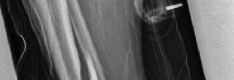

Tibial shaft fractures extending into the distal metaphysis and the tibial plafond represent a formidable challenge in orthopedic trauma. Historically, these complex injury patterns—often classified as AO/OTA 43-B or C, or 42 with distal extension—were managed primarily with plate osteosynthesis due to concerns regarding articular congruity and the inability of early generation intramedullary nails to secure short distal segments. However, the evolution of intramedullary nailing systems, featuring multi-planar distal locking options and advanced insertion trajectories, has revolutionized the management of these fractures.

The epidemiology of these injuries demonstrates a bimodal distribution. High-energy trauma, such as motor vehicle collisions and falls from height, typically afflicts younger patients and presents with significant soft tissue compromise, comminution, and complex articular involvement. Conversely, low-energy torsional mechanisms are more frequently observed in the elderly population, often resulting in spiral fracture patterns that propagate into the joint.